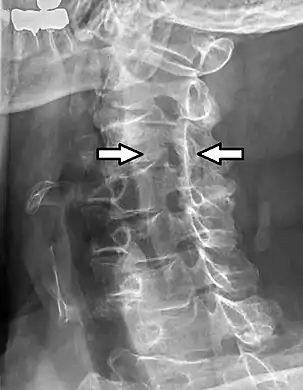

Oblique projectional radiograph of a man presenting with pain by the nape and left shoulder, showing a stenosis of the left intervertebral foramen of cervical spinal nerve 4, corresponding with the affected dermatome.

CT scan of a man presenting with radiculopathy of the left cervical spinal nerve 7, corresponding to spondylosis with osteophytes between the vertebral bodies C6 and C7 on the left side, causing foraminal stenosis at this level (lower arrow, showing axial plane). There is also spondylosis of the facet joint between C2 and C3, with some foraminal stenosis at this level (upper arrow), which appears to be asymptomatic.